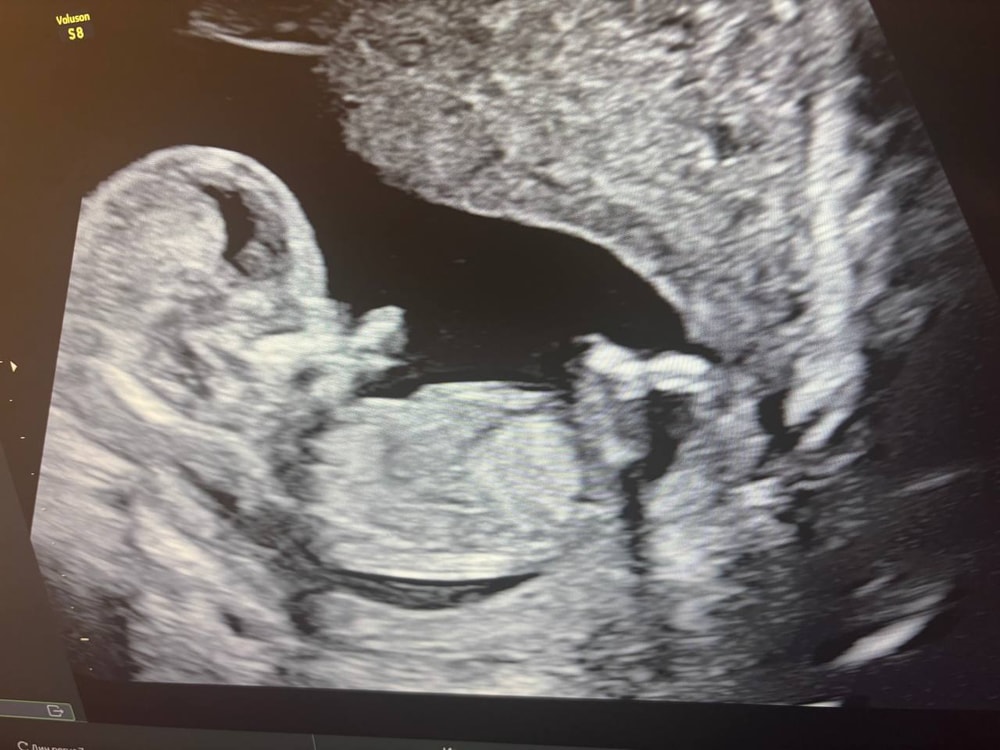

Девушки в регистратуре оказались очень милыми, все рассказали, да и в целом персонал мне понравился. Нам сказали, что от врача зависит разрешит ли мужу зайти тоже посмотреть и только в конце пускают. Немного расстроились изначально, но в итоге оказалось зря. Мне померили давление и потом отправили на УЗИ. Делали его мне около получаса, малыш показался во всей красе изначально. И так повернется, и сяк, и ручкой помашет и пальчики в рот положит (см. фото 1,2). Врач сказала, что малыш отлично развит для срока, все у него в норме, послушали сердечко, посчитали пальчики, похвалили наш профиль, сказали, что красивый))))) Зовут нашего папу тоже посмотреть и тут начинается самое интересное. Как только муж садится и начинаем смотреть, булочка, устав от внимания, демонстративно отворачивается и мы во всей красе лицезреем попку и спинку))) ну вот спасибо))) Врач уже и так, и так пыталась растормошить его, но максимум на что удалось его подбить, это посмотреть на нас через плечо, видимо с мысль "да отстаньте вы уже от меня" (см. фото 3). Но было прям очень забавно это, особенно учитывая тот факт, что это уже не первые его(ее) прятки с папой. То допплером при нем сердечко не могу найти, то сейчас вот спрятался.